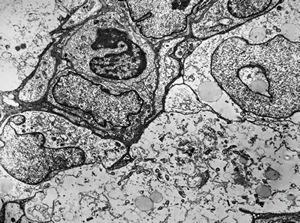

M,10y. | herpetic encephalitis